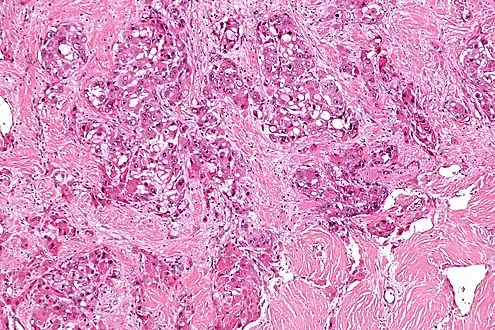

Micrograph of fibrolamellar hepatocarcinoma showing the characteristic laminated fibrosis between the tumor cells with a low NC ratio. H&E stain.

The histopathology of FHCC is characterized by laminated fibrous layers, interspersed between the tumor cells. Cytologically, the tumor cells have a low nuclear to cytoplasmic ratio with abundant eosinophilic cytoplasm. Tumors are non-encapsulated, but well circumscribed, when compared to conventional HCC (which typically has an invasive border).